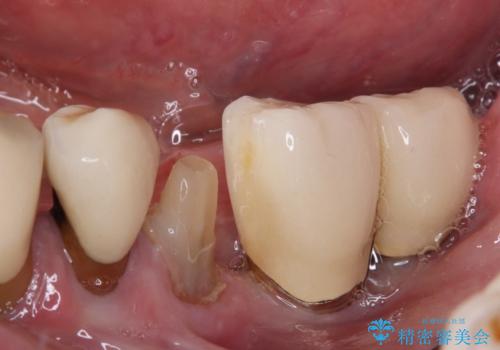

- 奥歯が割れてしまい、抜歯が必要となった患者様です。

以前にも歯が割れてインプラント治療を行いましたが、抜歯してからインプラント埋入→仮歯装着までに半年以上を要し、その間に残された歯への負担が大きくなり、左右反対側のセラミッククラウンが破折したことがありました。

そのため、当院に新しく導入した手法により、抜歯をした日にインプラントを埋入し、そのままを仮歯を装着することで、他の歯への負担を軽減する計画を立てました。